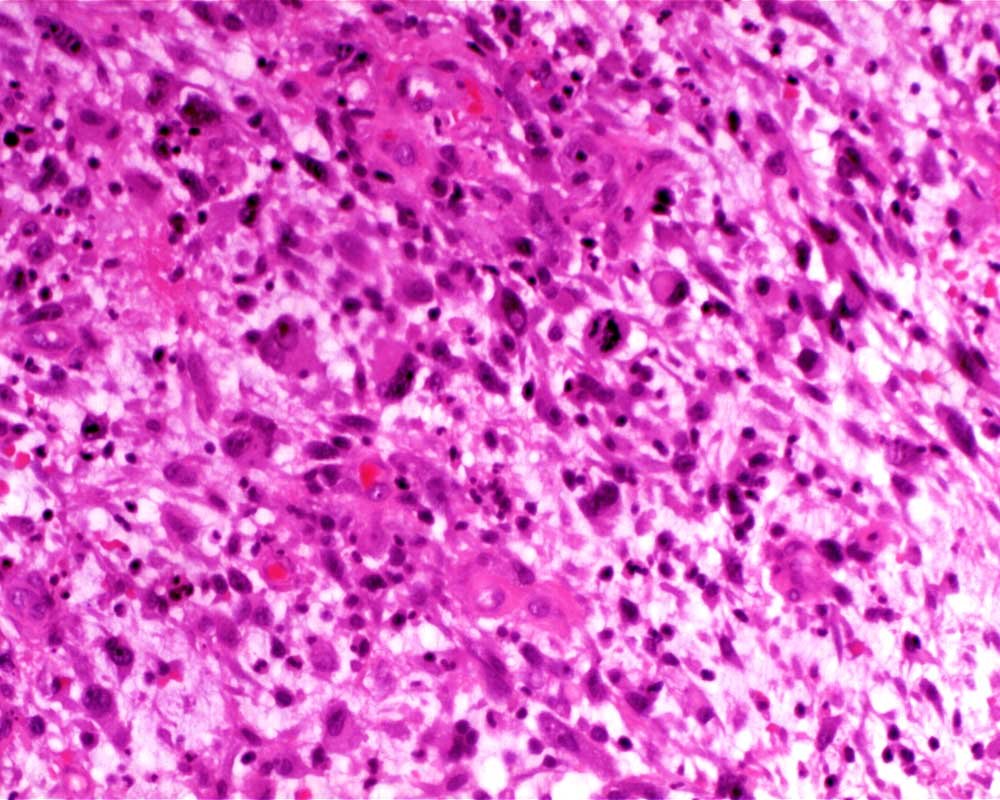

Case: LegMass

Final Diagnosis: